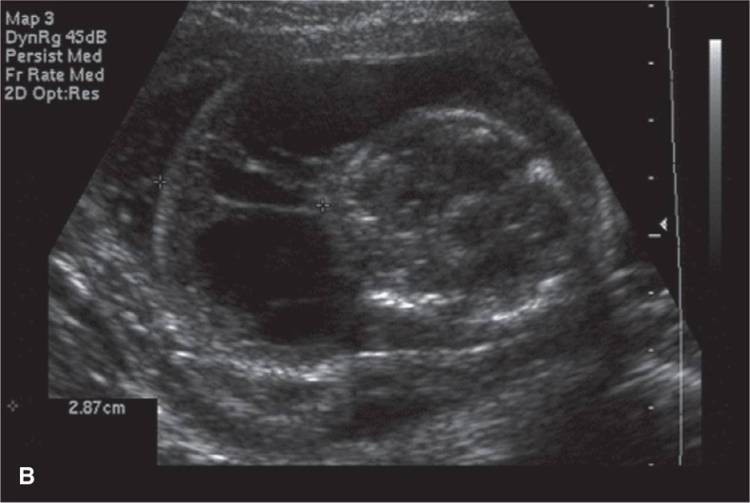

El ultrasonido ginecológico es una técnica de imagen no invasiva que se utiliza para evaluar los órganos reproductivos femeninos, incluyendo el útero, los ovarios y las trompas de Falopio. Esta técnica utiliza ondas sonoras de alta frecuencia para producir imágenes detalladas de estos órganos, lo que permite a los médicos detectar cualquier anormalidad o afección que pueda estar presente.

El ultrasonido ginecológico se utiliza para diagnosticar y evaluar una amplia variedad de afecciones ginecológicas, como fibromas uterinos, quistes ováricos, endometriosis y cáncer de ovario. También puede utilizarse para monitorear el desarrollo de un embarazo y detectar cualquier problema que pueda surgir.